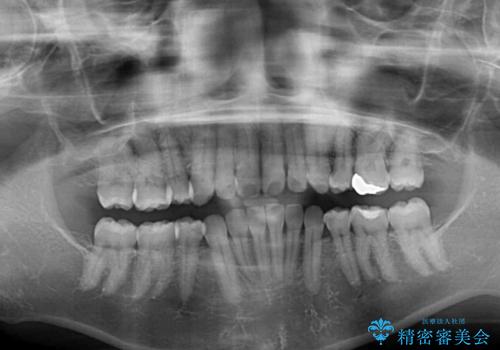

- 上下前歯の叢生を気にして来院された患者様です。

費用を抑え、期間もあまりかけずに治療をしたいとのことで、インビザライン・ライトを用いて矯正治療を行うこととしました。

インビザライン・ライトは、製作できるアライナーの枚数に制限があるため、移動可能な量に限りがあります。

一方で、半年程度で治療を終えることができるため、軽度の歯列不正の患者様には大変お勧めです。